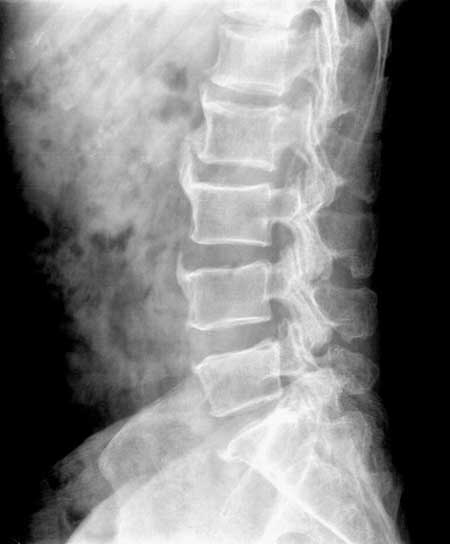

退行性骨关节病。

腰椎诸椎体前纵韧带广泛骨化及韧带附着的椎体前面骨质增生,符合dish病。

也就是特发性骨质增生..